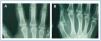

En enero de 2006, presentó HPTS grave (con niveles más elevados de iPTH que los presentados en los meses anteriores). La ecografía paratiroidea reveló una imagen seudonodular hiperecogénica en la zona posteromedial del lóbulo tiroideo izquierdo, que era compatible con una hipertrofia de la glándula paratiroidea. Una serie radiológica mostró signos de hiperparatiroidismo en los huesos de ambas manos y muñecas y CV en las arterias radiales e interdigitales. En la mamografía se observaron múltiples CV lineales en ambas mamas (figura 1A, figura 2A, figura 3A y figura 4A; imágenes de las manos y de las glándulas mamarias en 2006).

Durante este período, se pudo observar que en la serie radiológica las calcificaciones de la arteria interdigital habían desaparecido y que el hueso presentaba un aspecto más estructurado (figura 1B y figura 2B; imagen de la mano, 2007). También la mamografía mostró una regresión de las CV. Las calcificaciones lineales iniciales fueron sustituidas por calcificaciones irregulares (figura 3B y figura 4B; glándulas mamarias en 2007).

Figura 1. (A) Imagen radiográfica anteroposterior de la mano izquierda en el año 2006. (B) Imagen radiográfica anteroposterior de la mano izquierda en el año 2007.

Figura 2. (A) Imagen radiográfica anteroposterior de la mano derecha en el año 2006. (B) Imagen radiográfica anteroposterior de la mano derecha en el año 2007.